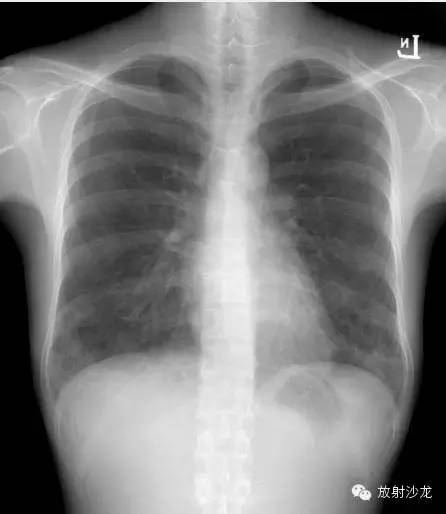

首次就诊胸片:

胸片示两肺中下野边界不清的磨玻璃样阴影(GGO)。CT示两肺地图样分布的GGO,主要位于两肺上叶、右肺中叶及两肺下叶,其中两肺下叶多发的GGO融合并伴有小叶间隔增厚。2周后随访胸片示双肺野弥漫分布的GGO增多。患者第一次就诊时未告知自己的性取向。只告知了曾接触过染发剂。患者按肺间质性疾病给予激素治疗。然而,治疗后患者的症状和影像学表现均加重。患者血液检测结果显示艾滋病病毒阳性。支气管肺泡灌洗液GMS染色示大量的卡氏肺孢子虫。